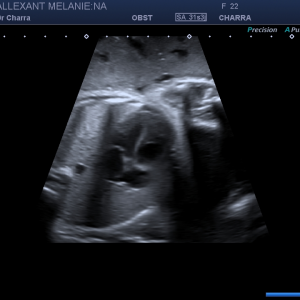

Suivi de votre grossesse avec réalisation des échographies recommandées, Prise en charge des IVG medicamenteuses (en lien avec la maternité de Beaune), infertilité, prise en charge des douleurs pelviennes (endométriose par exemple)

Diplômée en Echographie foetale et Gynécologique

Agrément National pour la réalisation des échographies du Premier Trimestre de grossesse